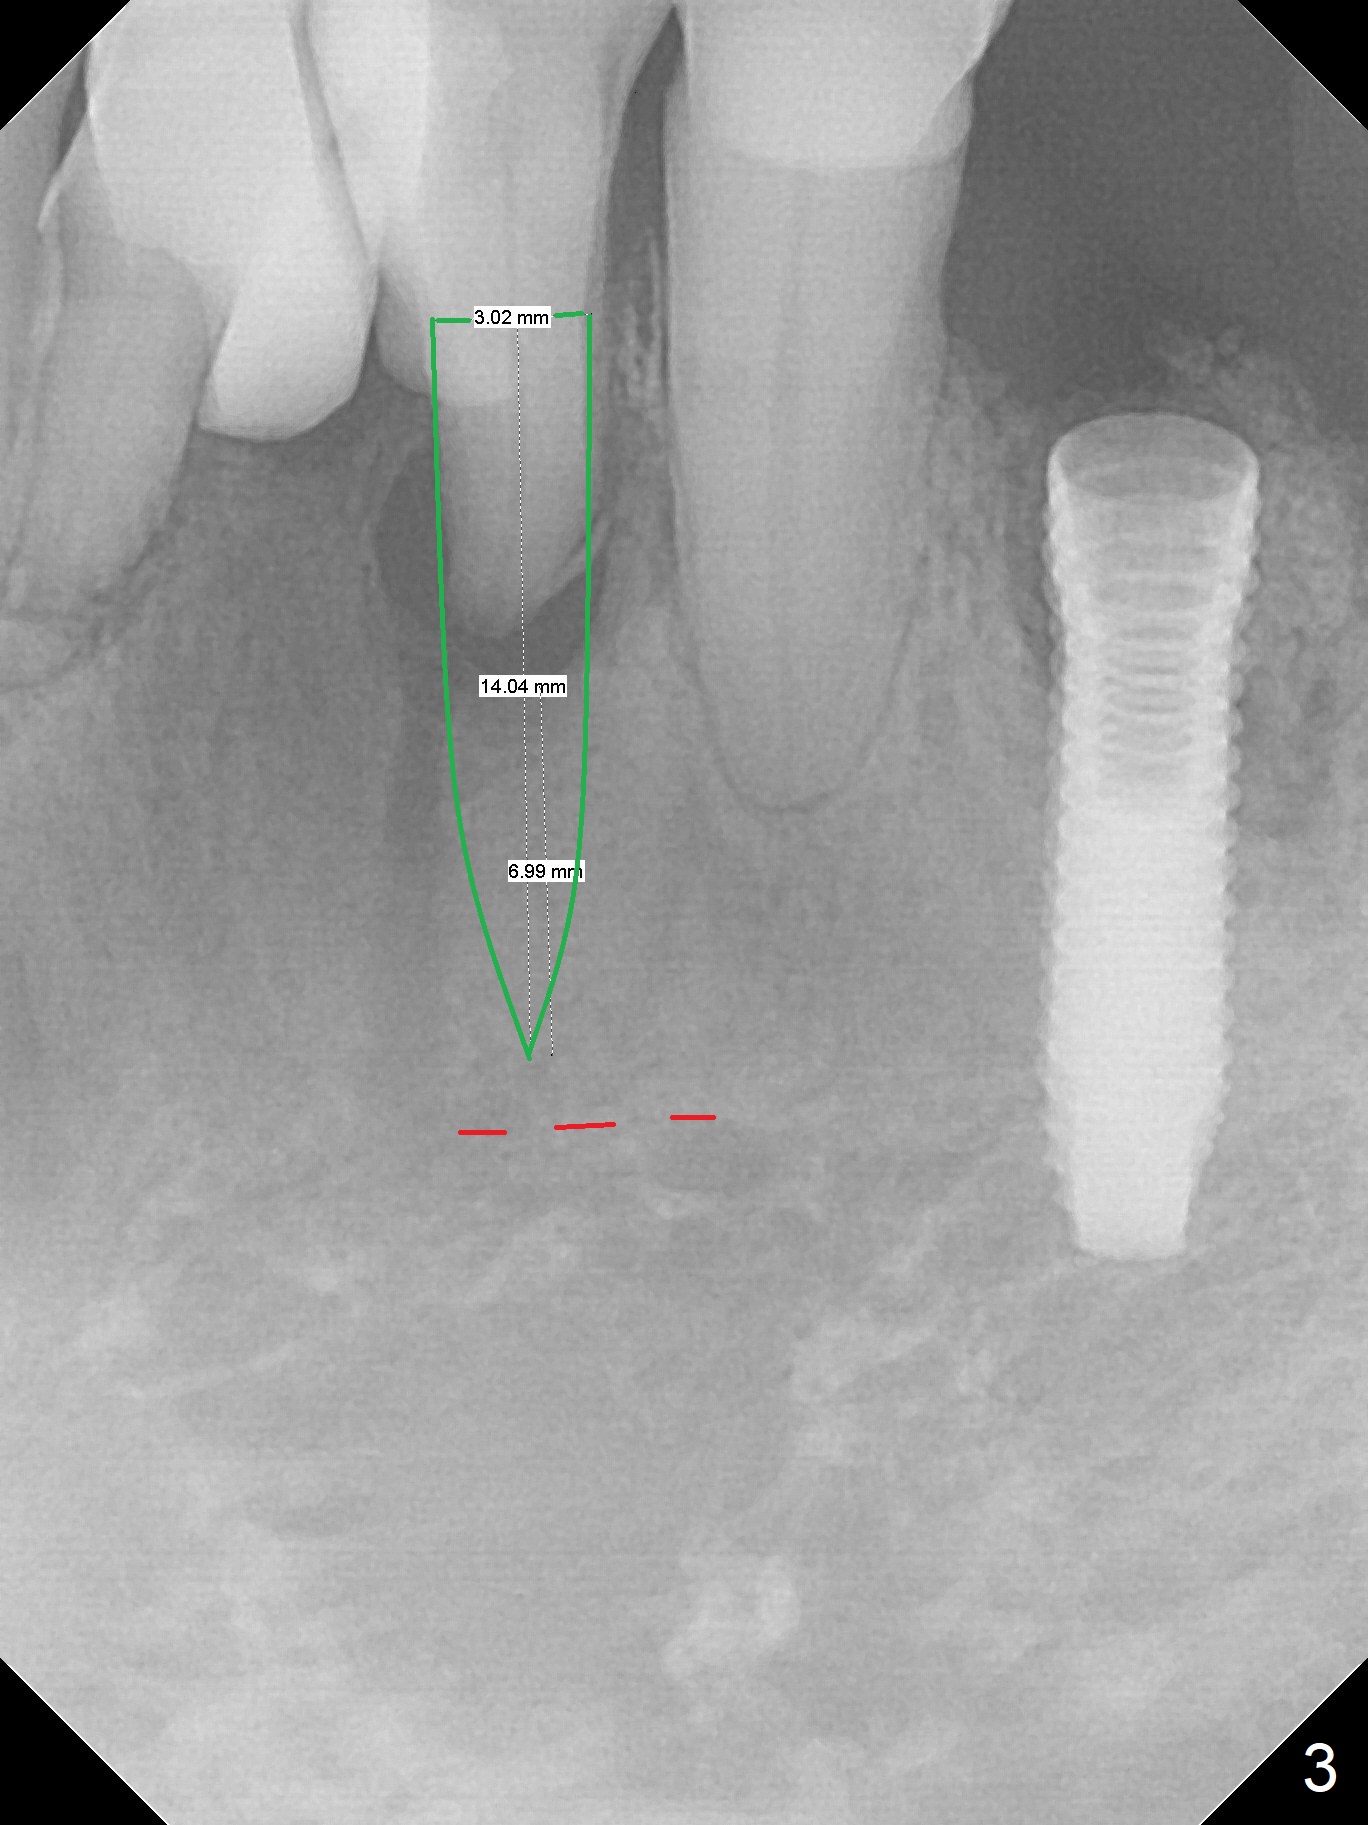

A 73-year-old man will return for #23 and 25 implants following ones at #21 and 31. Probably due to large periapical radiolucency at #23 (Fig.1 yellow dashed line), the terminal branch (pink) of the Incisive Canal (red) is distinct. Postop hemorrhage occurs associated with placement of a long implant at #. To prevent the complication at #23, a 14 mm long 1-piece implant (Fig.3) seems to be safer than 16 mm one (Fig.2). Seven mm in the native bone (Fig.3) should provide with sufficient primary stability. A temporary crown will be fabricated at #31. If the provisional at #21 is unstable, impression may be necessary for #21 and 31. Initiate osteotomy using visual and tactile acuity and double check the position and trajectory with RPD and X-ray. It might be preferable to extract the malpositioned incisor to give the remaining one the best 3-dimensional reference. Prepare 2 of 1-piece implant kits as well as angled one.